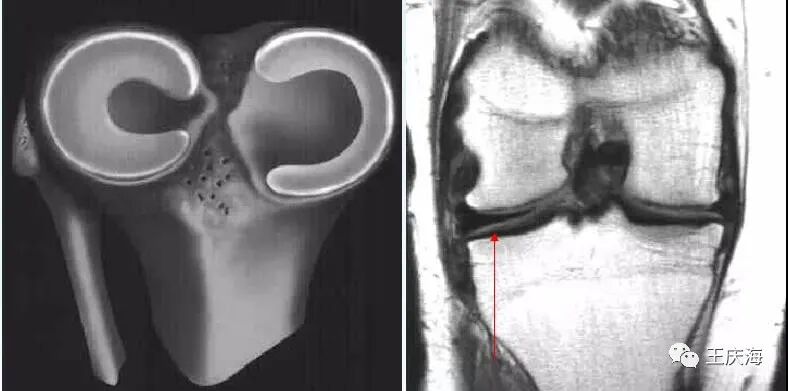

小盘状半月板

冠状面(图A)见外侧半月板体部宽度增宽,横断面(图B)示外侧半月板环较小。